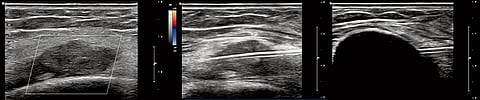

For the country, where late diagnosis remains common, cryoablation could be particularly useful in managing small, early-stage tumours. Dr Sachin Sekhar Biswal, medical oncologist at Manipal Hospitals, said although cryoablation as a precision approach is not new, MRI-guided cryoablation with high resolution imaging has taken a giant leap.

“MRI targeting in real time ensures high accuracy. Early stage tumours where radical surgery is considered, can be approached with cryoablation and with good functional recovery and without having to sacrifice the organ and physiological function,” he said.